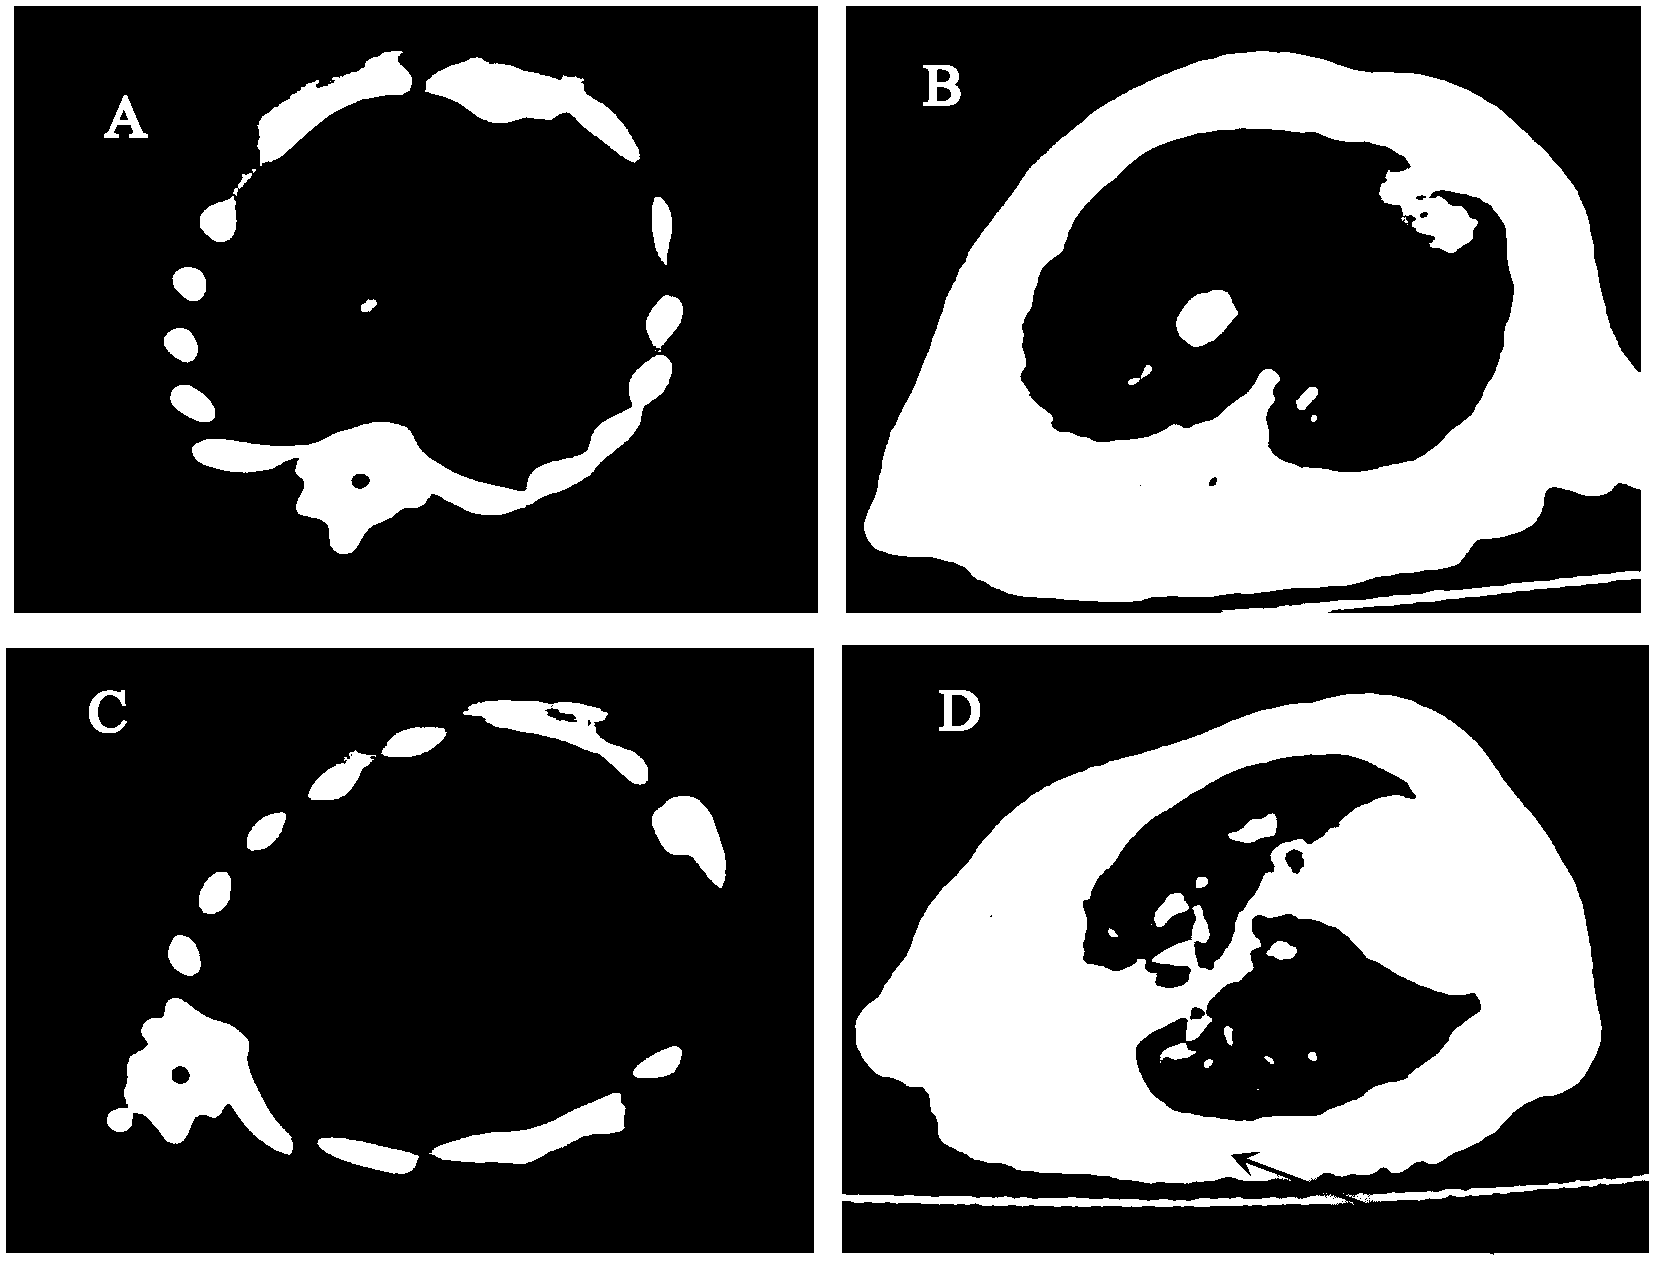

摘要: | 本发明提供了一种细胞株蛋白在制备预防或治疗哺乳动物肺纤维化疾病的药物中的用途。其中,所述细胞株蛋白为人源细胞株蛋白,所述用途为预防或治疗特发性肺纤维化疾病中的用途。本发明提供的重组人源Cygb意外地其可以治疗特发性肺纤维化。因此,本发明公开了重组人源细胞株蛋白(rhCygb)可作为治疗肺纤维化的基因工程药物中的用途,其必将带来良好的社会效益和经济效益。 | ||||